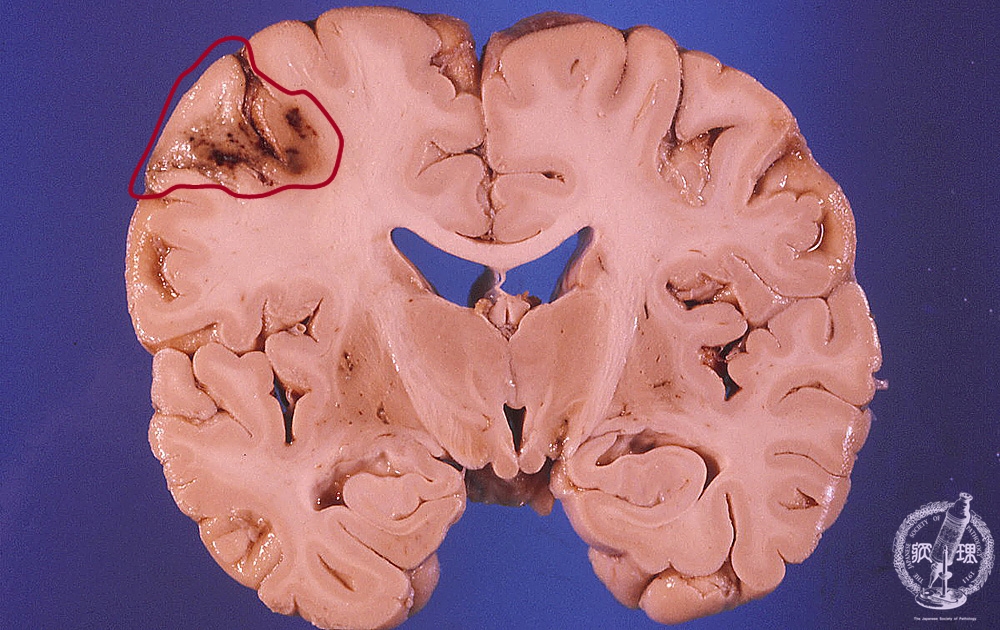

- ★(2)Cerebral infarction

Macroscopic findings: Localized hemorrhagic infarction was detected in left frontal and temporal lobes. Infarcted region appeared dark brown in color surrounded by massive edema with compression of the gyri and narrowing of the sulci.